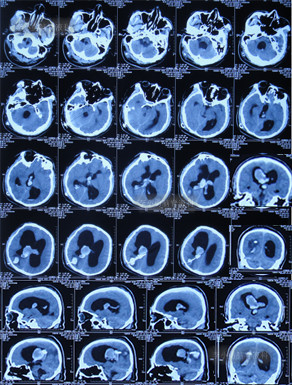

发现脑积水11年即2016年7月20日,复查头颅CT(图-2)后,仍建议继续定期观察。

图-2:2016年7月20日头颅CT